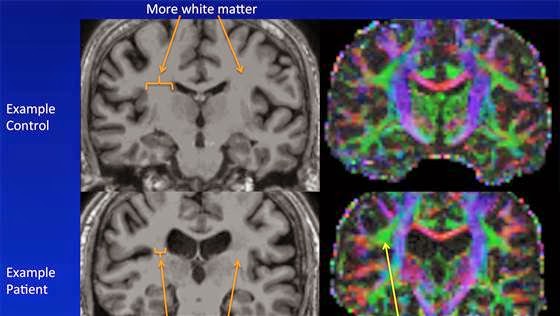

Investigadores de radiología han descubierto que el contenido global de la materia blanca de cerebros de pacientes con SFC en comparación con la de los cerebros de sujetos sanos era menor.

Los investigadores encontraron que el volumen de

materia blanca (células de las fibras nerviosas cerebrales) fue menor en el

grupo con SFC. También

hubo algunas diferencias en el lado derecho del cerebro en las fibras nerviosas

que conectan el temporal a las regiones frontales del cerebro.

Los investigadores encontraron que, en promedio, las personas con

SFC tenían un menor volumen total de materia blanca (células de fibras

nerviosas) en su cerebro que las personas sin.